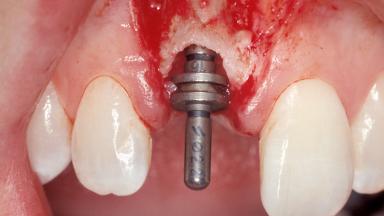

Immediate Placement of an Implant in a Maxillary Right Central Incisor Site

A 30-year-old female patient was referred to the office for the treatment of tooth 11. Her chief concern at the initial visit was to inquire, “Why is my tooth pink?” Upon clinical examination, it was determined that tooth 11 had a previous history of trauma and that the clinical crown had become noticeably pink in color as a result of internal resorption. This diagnosis was confirmed radiographically, indicating a large radiolucency involving the central and distal portions of the clinical crown. It was determined that restoration of this tooth was not possible, and that extraction was indicated. The presence of a mid-line diastema, which the patient wanted to reproduce, directed the treatment plan for tooth replacement utilizing a dental implant.

| Placement Protocol | Immediate implant placement |

| Tooth Site | Maxillary incisor or canine |

| Socket Morphology | Single-root socket |

| Socket Integrity | Sufficient, with intact bone walls |